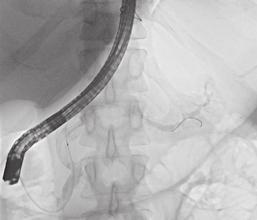

Na našem pracovišti pacient podstoupil v rámci dalšího došetření endosonografické vyšetření s ERCP v květnu 2024. Na EUS byl popsán atrofický pankreas s dilatací pankreatického vývodu v celém jeho rozsahu s maximem v krčku, v němž byl zobrazen nález vakovité dilatace na 16mm s obsahem izoechogenní vlající hmoty. Dle kontrastního EUS vyšetření se jedná o viabilní tkáň. Následně bylo přistoupeno k provedení ERCP. Vaterská papila byla dilatovaná s protruzí mucinu – obraz fish eye (obr. 1). Po kanylaci pankreatického vývodu byla aplikována kontrastní látka – obraz vakovité dilatace ductus pancreaticus v rozsahu krčku pan-

Obr. . ERCP " dilatace PD v hlav a t le s defektem v n·plni.

Fig. . ERCP ! PD dilatation in the head and body with a filling defect.